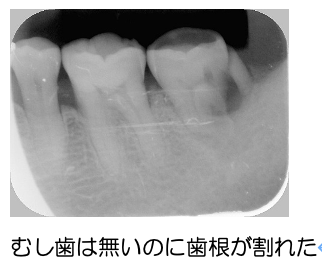

ナイトガードがあなたの歯を守る

―疲労破折から歯を守るー

このような方はマウスピースをして歯を保護しましょう。ご飯を食べるときよりも無意識に噛みしめたり、寝ているとき歯ぎしりをしたり食いしばることが危険であると言われています。